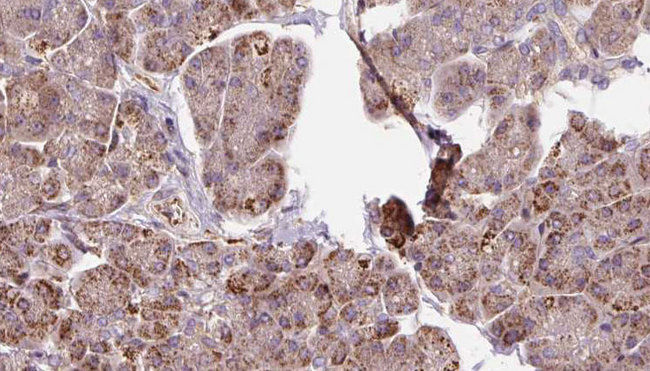

- Main image

- Experimental details

- 1:100 staining human pancreas carcinoma tissue by IHC-P. The sample was formaldehyde fixed and a heat mediated antigen retrieval step in citrate buffer was performed. The sample was then blocked and incubated with the antibody for 1.5 hours at 22°C. An HRP conjugated goat anti-rabbit antibody was used as the secondary.